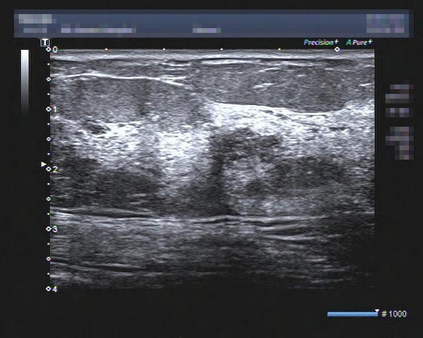

Ultrasonography is an important routine examination for breast cancer diagnosis, due to its non-invasive, radiation-free and low-cost properties. However, it is still not the first-line screening test for breast cancer due to its inherent limitations. It would be a tremendous success if we can precisely diagnose breast cancer by breast ultrasound images (BUS). Many learning-based computer-aided diagnostic methods have been proposed to achieve breast cancer diagnosis/lesion classification. However, most of them require a pre-define ROI and then classify the lesion inside the ROI. Conventional classification backbones, such as VGG16 and ResNet50, can achieve promising classification results with no ROI requirement. But these models lack interpretability, thus restricting their use in clinical practice. In this study, we propose a novel ROI-free model for breast cancer diagnosis in ultrasound images with interpretable feature representations. We leverage the anatomical prior knowledge that malignant and benign tumors have different spatial relationships between different tissue layers, and propose a HoVer-Transformer to formulate this prior knowledge. The proposed HoVer-Trans block extracts the inter- and intra-layer spatial information horizontally and vertically. We conduct and release an open dataset GDPH&GYFYY for breast cancer diagnosis in BUS. The proposed model is evaluated in three datasets by comparing with four CNN-based models and two vision transformer models via a five-fold cross validation. It achieves state-of-the-art classification performance with the best model interpretability.

翻译:超声波分析是乳腺癌诊断的一个重要常规检查,原因是其非侵入性、无辐射和低成本的特性。然而,由于其内在局限性,它仍不是乳腺癌的第一线筛选测试。如果我们能够精确地通过乳房超声图像诊断乳腺癌(BUS),它将是一个巨大的成功。我们提出了许多基于学习的计算机辅助诊断方法,以实现乳腺癌诊断/感官分类。然而,其中多数方法需要事先确定性能模型,然后对ROI内部的跨值进行分类。常规分类支柱,如VGG16和ResNet50等,可以在没有ROI要求的情况下实现有希望的分类结果。但是这些模型缺乏可解释性,从而限制了其在临床实践中的使用。在本研究中,我们提出了一个新的无乳腺癌诊断模型,在超声波图像中进行解释性特征描述。我们利用了先前的解剖学学学知识,即恶性肿瘤和良性肿瘤模型在不同组织层之间有着不同的空间关系,并提议采用状态解析法来编制这一先前的知识。拟议中的HOVer-Trans-Trading-Tradef-trainal Ex-deal-dealal-deal-deal-deal-degraphal-deal-deal-deal-deal-deal-deal disal disal-dal-dal-dal-dal-dal-deal-deal-dal-deal-deal-deal-dal-dal-dal-dal-dal-dal-dal-dal-dal-dal-dal-dal-dal-dal-I-dal-Iversal-dal-Ial-d-d-I-d-d-I-I-I-I-I-I-I-I-I-I-I-I-I-I-I-I-I-I-I-I-I-I-I-I-I-Ial-I-Ial-Ial-I-I-I-I-I-I-I-I-I-I-I-I-I-I-I-I-I-I-I-I-I-I-I-I-I-I-I-I-I-I-I-I-